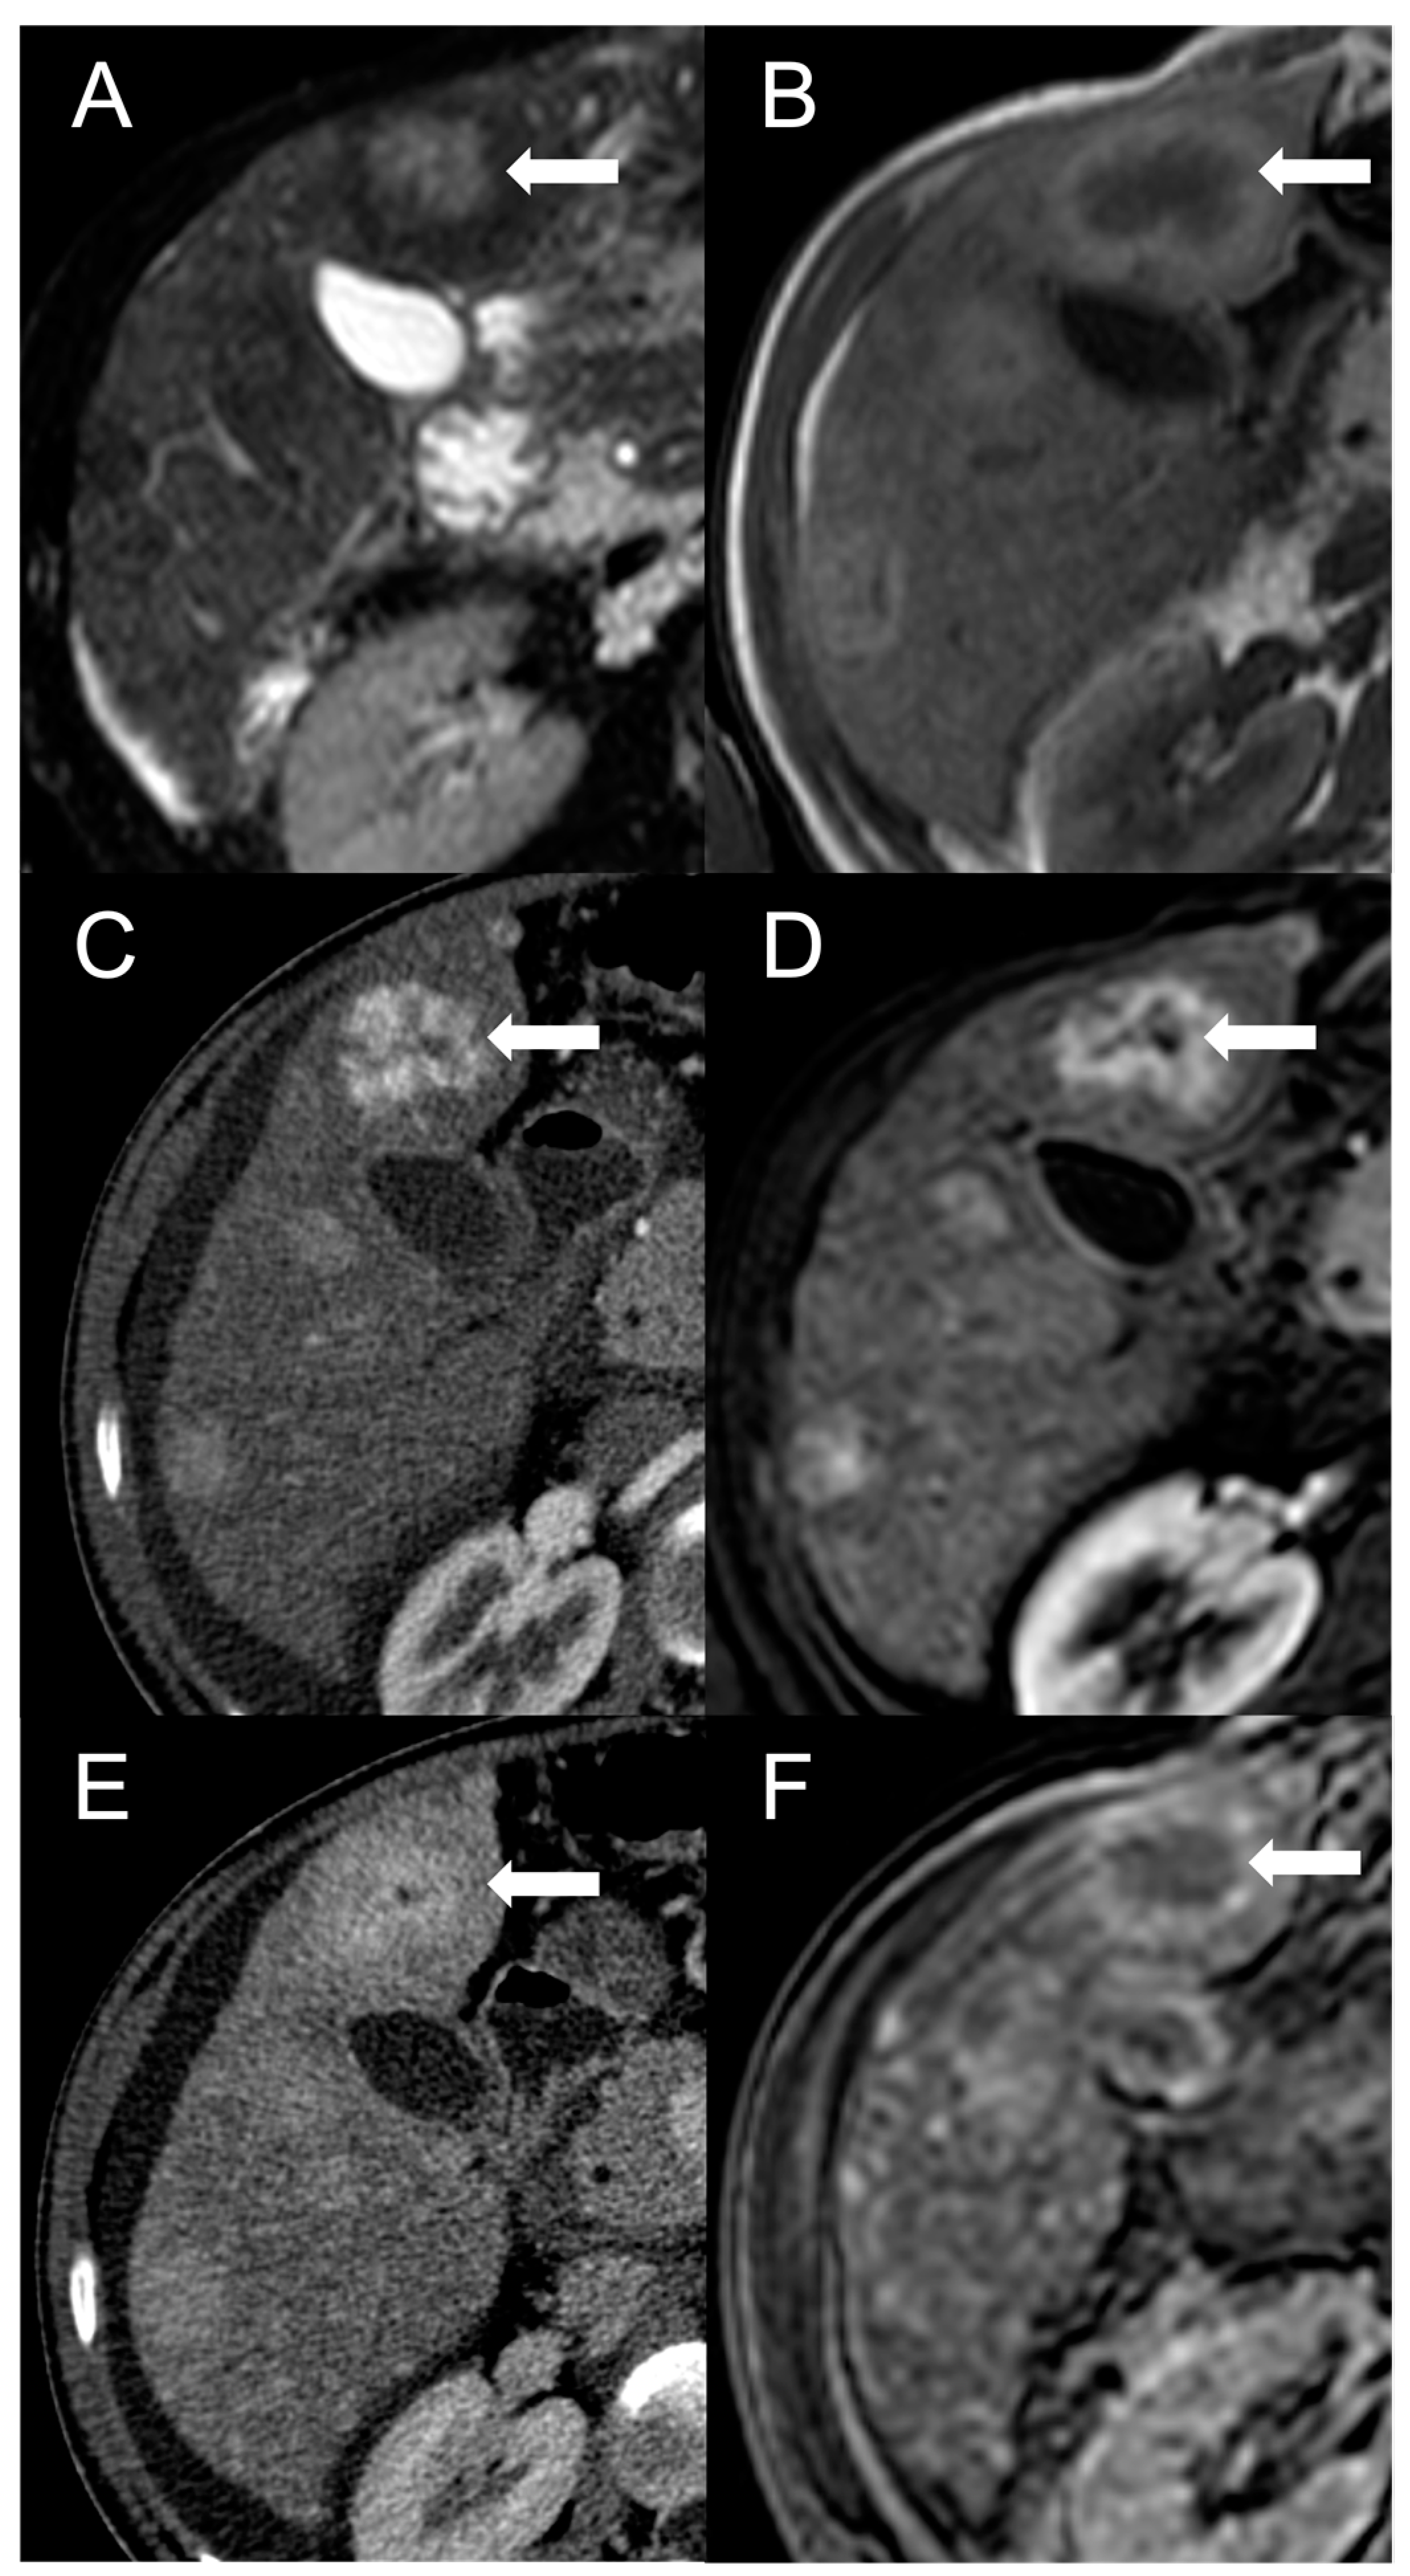

Figure 2.

FNH-like RN with central scar (arrow) in a 34-year-old male patient with Budd–Chiari syndrome. In MRI, the scar is typically hyperintense on fat-saturated T2-weighted images (A) and hypointense in T1-weighted images (B). In the arterial phase after contrast agent administration, the scar can be identified as a central stellate area that appears hypodense in CT (C) and hypointense in MRI (D). In the CT delayed phase, the nodule shows increased density, but a central hypodense component representing the scar remains visible (E). In gradient-echo T1-weighted images acquired in the hepatobiliary phase (F), the scar is clearly depicted as a central low-signal area.

The presence of a central scar is another common finding in FNH-like RNs, particularly in those larger than 1 cm [10]. This scar typically appears as a hypointense, central stellate area on fat-suppressed T1-weighted imaging and a hyperintense area on T2-weighted imaging (Figure 2). Moreover, since regenerative nodules are made up of normal hepatocytes, they appear isointense or slightly hyperintense to the adjacent liver parenchyma on diffusion-weighted imaging, and there is no significant reduction in the diffusion values observed on the ADC map. These characteristics help to differentiate between regenerative and HCC nodules with reasonable confidence in patients with BCS.